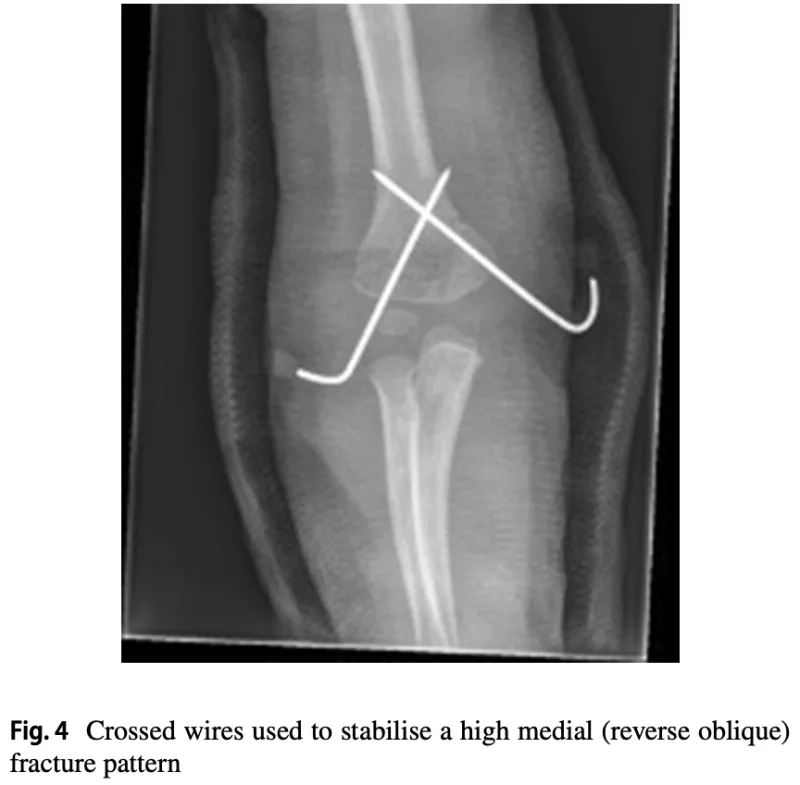

私が, 骨折してズレた骨を元の位置に戻して保持したところで, 後輩医師に針金(鋼線)を骨にドリルで刺し込んでもらいました.